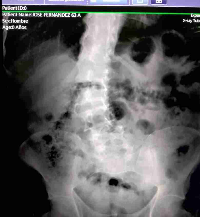

Bom dia a todos. Deus abençoe vcs. Antes de tudo quero pedir desculpas por incomodar vocês. O objetivo desta vaquinha é poder ajudar meu pai quien mora na Venezuela, e encuentra-se com a saúde debilitada, ele precisa de um tratamento para a coluna e, após uma série de exames, foi diagnosticado com uma deficiência nas artérias que bombeiam sangue e oxigênio para o coração, o que causa fortes dores de cabeça, tonturas e até desmaios, ele também está com fígado inflamado e gorduroso, pedras nos rins e colesterol elevado.Por isso ele precisa de um tratamento muito caro e deve seguir uma dieta rigorosa por pelo menos 15 dias, e devido ao problema na coluna meu pai não pode trabalhar. Devido à difícil situação do país, que não é segredo para ninguém, é muito difícil conseguir medicamentos, sendo totalmente impossível ser atendido em hospital público, onde para tomar injeção de dipirona é necessário levar o álcool, injectadora o algodão e a dipirona. E no momento eu não posso le ajudar financeiramente pois devido as rotinas de fisioterapia do meu bebê que tem Síndrome de Down tive que parar de trabalhar.Pido por favor me ajude, qualquer valor é muito importante, agradeceria do fundo do meu coração. Deus abençoe vcs.